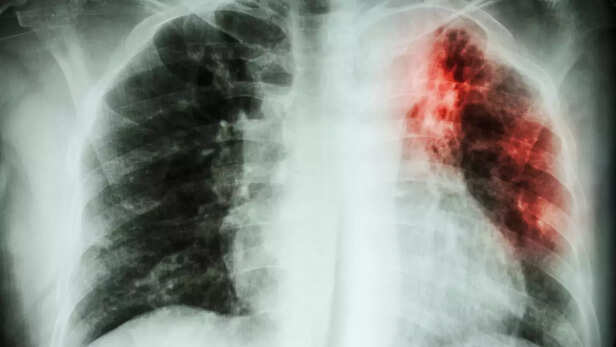

हमारे शरीर का प्रतिरक्षा तंत्र हर समय रोगजनक जीवाणुओं से लड़ता रहता है। लेकिन, प्रतिरक्षा तंत्र जैसे ही कमजोर होता है, तो बीमारियां हावी होने लगती हैं। ऐसी ही, बीमारियों में से एक है टीबी की बीमारी। जिसे तपेदिक या क्षय रोग के नाम से भी जाना जाता है। टीबी का पूरा नाम ट्यूबरक्लोसिस है, जो 'माइकोबैक्टीरियम ट्यूबरक्लोसिस' नामक जीवाणु से होता है। टीबी रोग मुख्य रूप से फेफड़ों को नुकसान पहुँचाता है। हालांकि, टीबी का वायरस आंत, मस्तिष्क, हड्डियों, जोड़ों, गुर्दे, त्वचा तथा हृदय को भी प्रभावित कर सकता है।

फेफड़े की टीबी में चिल्लाना, गाना गाना, जोर जोर से खांसना या हंसना, बातचीत करना, इस दौरान जो बलगम के ड्रॉपलेट के साथ बैक्टीरिया बाहर आता है, जिससे लोगों में इंफेक्शन फैलता है।